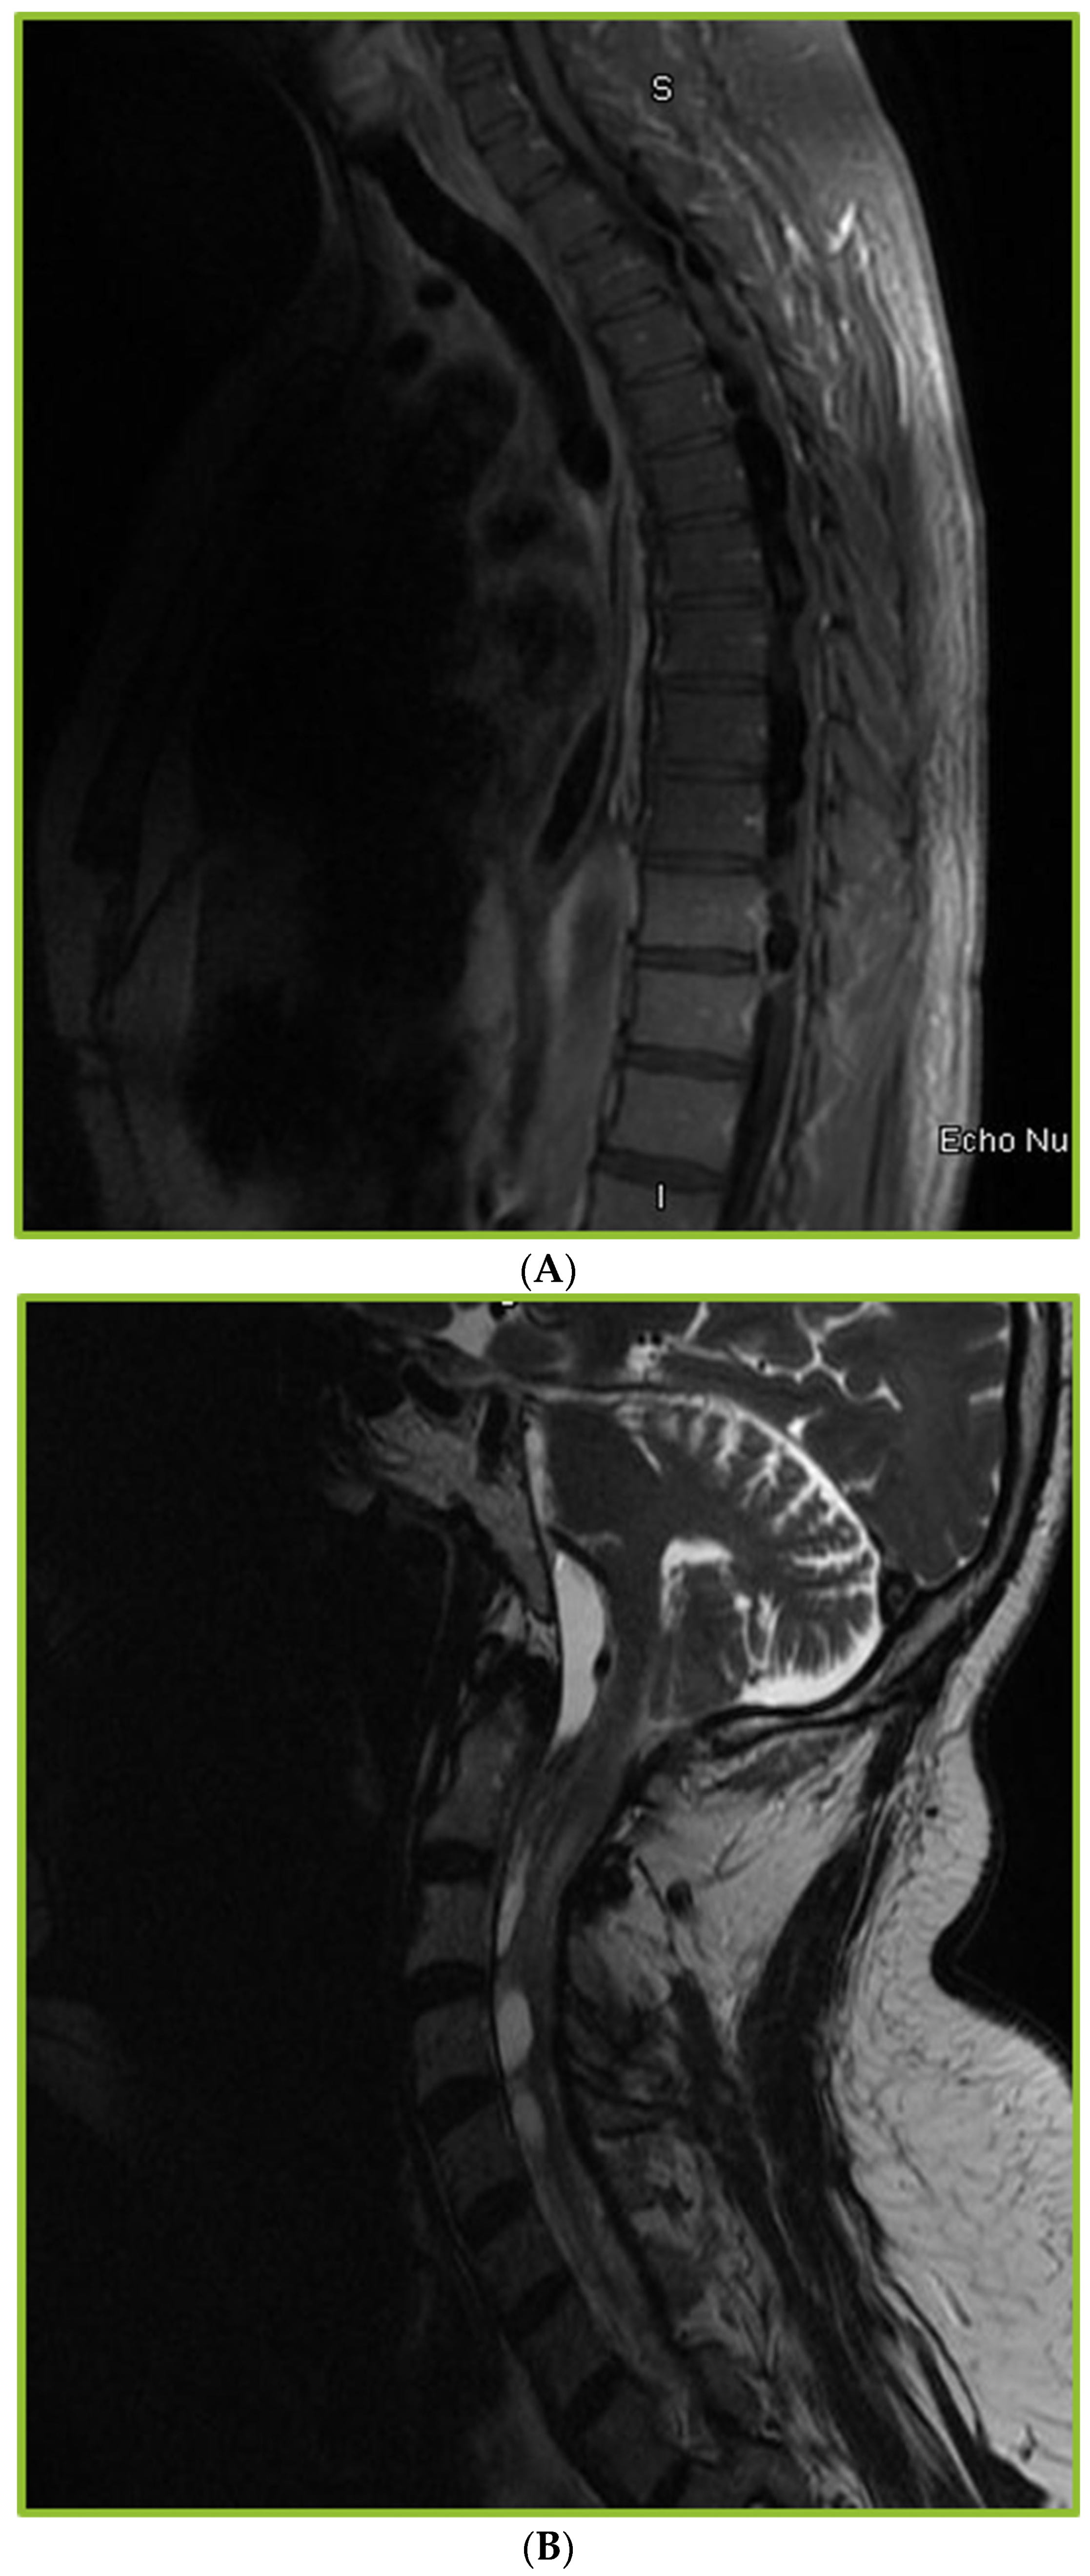

Spinal Arachnoiditis in Patients with Coccidioidomycosis Meningitis—Analysis of Clinical and Imaging Features